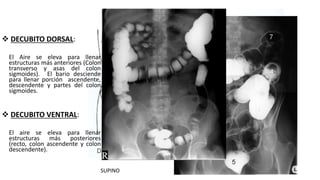

 DECUBITO DORSAL:

El Aire se eleva para llenar

estructuras más anteriores (Colon

transverso y asas del colon

sigmoides). El bario desciende

para llenar porción ascendente,

descendente y partes del colon

sigmoides.

 DECUBITO VENTRAL:

estructuras más posteriores

(recto, colon ascendente y colon

descendente).